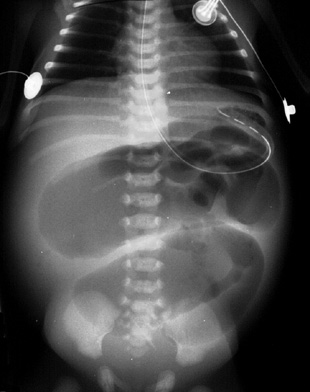

Jejunal-ileal atresia is a segmental atresia of the jejunum or the ileum. It is associated with malrotation and volvulus (25%) and cystic fibrosis (10%). Patients present within the first days of life with vomiting or a distended abdomen. |

Multiple distended loops of bowel. |